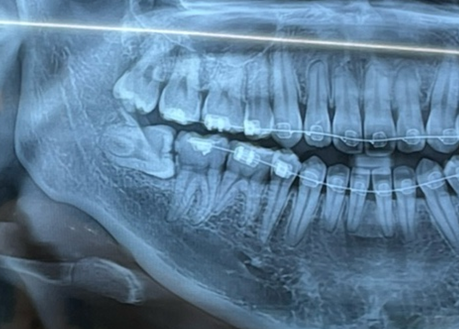

보이시나요.. 제 사랑니 ㅠㅠ (참고로 저는 교정중이랍니다.)

저렇게 수직으로 사랑니가 나있는걸 보니 여간 별난게 아니네요.................